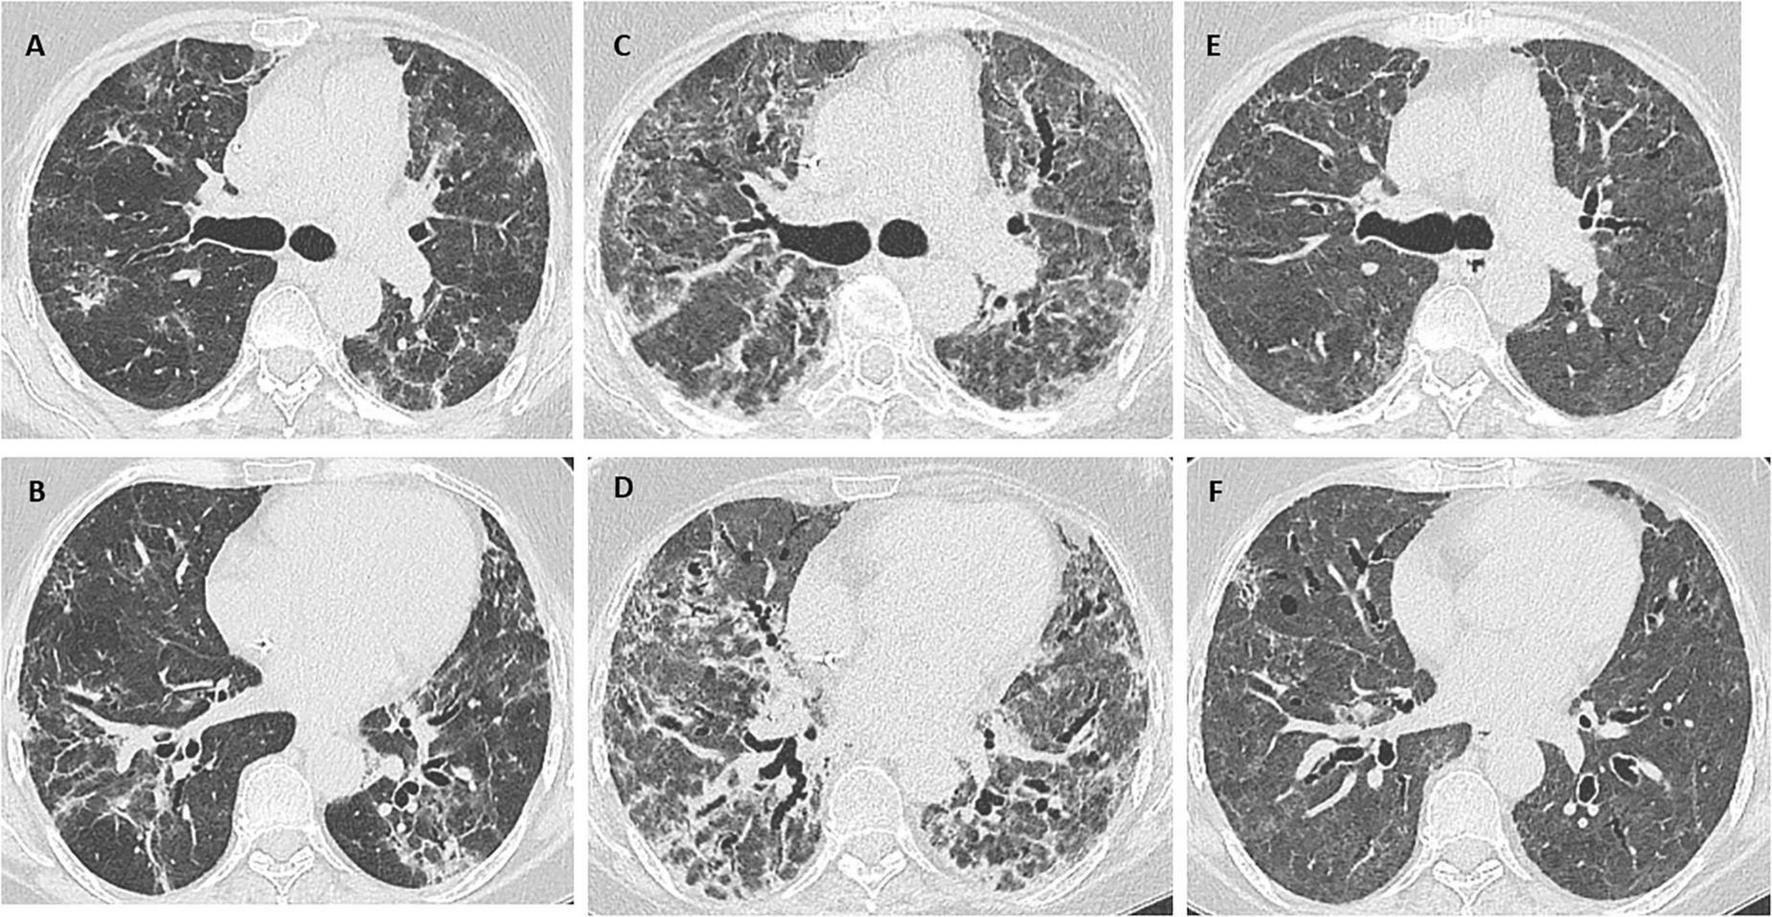

Chest x-ray revealed bilateral diffuse consolidation, and a chest computed tomography scan showed diffuse opacities in both lung fields, possibly associated with organizing pneumonia or an infectious process in the context of underlying fibrotic interstitial lung disease (Figures 1A, B). Given the radiology findings and the suspicion of acute exacerbation of interstitial lung disease, methylprednisolone 1 mg/kg/d, piperacillin-tazobactam, and azithromycin were started, and the patient was referred to the pulmonology department. She reported no workplace or environmental exposure or other regular medication. Serology testing for autoimmunity yielded negative results (Table 1). After a multidisciplinary meeting, we opted for PET-CT to rule out hematologic recurrence.

FIGURE 1

(A,B) Chest CT scan: diffuse opacities in both lung fields, possibly associated with organizing pneumonia or an infectious process in the context of underlying fibrotic interstitial lung disease. (C,D) Marked worsening of the interstitial lung disease with an associated extensive fibrotic component. (E,F) Considerable improvement in interstitial lung disease, with persistent, mildly diffuse ground glass opacity. Note also traction bronchiectasis and bronchiolectasis with no clear areas of honeycombing.

Her condition progressed slowly, thus requiring continued high-flow nasal cannula oxygen therapy. Endotracheal intubation was not considered appropriate because exacerbation of interstitial lung disease requiring intubation is associated with poor outcomes and high mortality rates. Another dose of rituximab was administered after 14 days, and a new chest CT scan revealed marked worsening of the interstitial lung disease, with an associated extensive fibrotic pattern (Figures 1C, D). As the patient’s condition remained unchanged, cyclophosphamide 500 mg IV was added as a single dose 3 weeks after admission, enabling oxygen therapy to be tapered, and the patient was transferred to the ward.

The patient was discharged with oxygen saturation of 92%–94% requiring nasal cannula oxygen therapy at 2 L/min. One month after discharge, she underwent chest CT (Figures 1E, F) and pulmonary function testing (Table 1). After a multidisciplinary committee discussion, she was eventually diagnosed with fibrosing unclassifiable interstitial lung disease. Biopsy was not considered appropriate because of the patient’s clinical condition, the persistent need for oxygen therapy, and weakness after a 2 months hospital stay. The patient tolerated inhaled treprostinil and mycophenolate 1,000 mg twice daily, and treatment with nintedanib was started. Corticosteroids were slowly tapered to prednisone 5 mg/d. Since recurrence of lymphoma was ruled out and there are no absolute contraindications, the patient is waiting to be evaluated for a lung transplant.